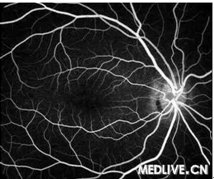

正常眼底荧光造影像

视网膜中央静脉阻塞